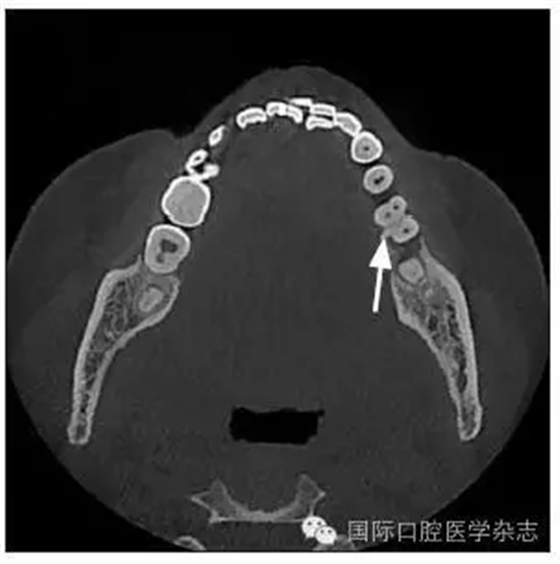

患者,女,42歲,因牙痛就診于中南大學(xué)湘雅醫(yī)學(xué)院附屬??卺t(yī)院牙體牙髓病科。臨床檢查為左側(cè)下頜第一磨牙遠(yuǎn)中齲,根尖壓痛和扣痛及頰側(cè)深牙周袋,牙髓電活力檢查陰性,近中根尖放射透明影。X線檢查根分叉區(qū)有不透明突起,扁形,

1.8 mm寬、8 mm長(圖1~3)。

圖1根分叉釉珠

Fig 1 Enamel pearl in furcation area

圖2 CT水平面觀

Fig 2 CT horizontal section view